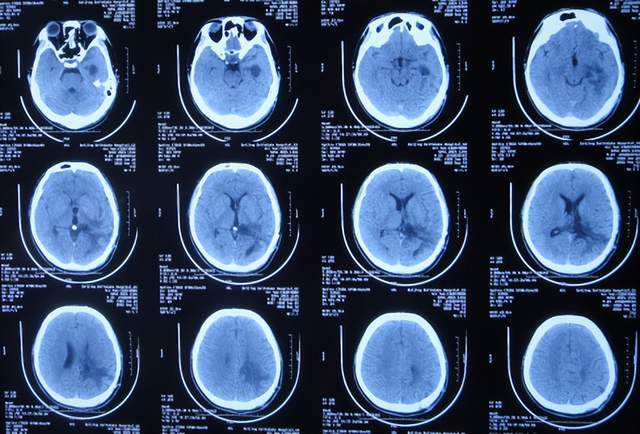

2021年3月8日(左颞角脑室腹壁外引流术后28天),进行了脑脓肿切除术(图-20)。

图-20:2021年3月8日头颅CT

2021年3月9日(左颞角脑室腹壁外引流术后29天,脑脓肿切除术后次日),查头颅CT示脑脓肿切除术后(图-21)。

图-21:2021年3月9日头颅CT

2021年3月12日(左颞角脑室腹壁外引流术后32天,脑脓肿切除术后5天),查头颅CT示仍有少量水肿(图-23)。

图-23:2021年3月12日头颅CT

但拔除引流管后11天即2021年4月6日,患者出现头痛,查头颅CT示颞角扩张(图-24)。

图-24:2021年4月6日头颅CT

因此于2021年4月8日,进行了脑室腹腔分流术;术后身体一切正常(图-25)。

出院后5个月即2021年9月中旬,出现偶尔头痛的症状,因此于出院后7个月后即2021年11月10日,第2次来到李小勇脑脊液科;入院时:时有头痛(图-26),身体其他正常;查头颅CT示左侧颞角扩张(图-27)。

图-27:入院时头颅CT

入院后2天即2021年11月12日,给予了颞角分流管调整术;术后第2天查头颅CT示颞角仍扩张(图-28)。

图-28:2021年11月14日头颅CT

入院治疗14天即2021年11月24日,查头颅CT示颞角缩小(图-29),患者头痛基本消失(图-30)。

图-29:2021年11月24日头颅CT

2022年1月4日(李小勇脑脊液科第2次治疗55天)出院。出院时:头痛已消失1月余(图-31),身体一切正常,查头颅CT示未见异常(图-32)。

图-32:出院时头颅CT